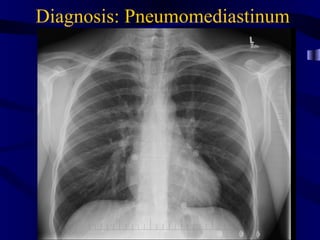

Pneumomed

Diagnosis: Pneumomediastinum